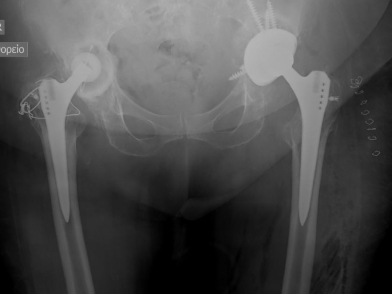

Η ολική αρθροπλαστική ισχίου (ΟΑΙ), είναι η αντικατάσταση της άρθρωσης του ισχίου και είναι μια εξαιρετικά επιτυχημένη χειρουργική επέμβαση που αποσκοπεί στην ανακούφιση του πόνου και στην αποκατάσταση της λειτουργικότητας σε ασθενείς που πάσχουν από σοβαρή αρθρίτιδα του ισχίου. H ολική αρθροπλαστική ισχίου δημιουργεί σημαντική βελτίωση της ποιότητας ζωής, ωστόσο ορισμένοι ασθενείς μπορεί να εμφανίσουν επιπλοκές. Μια σημαντική επιπλοκή είναι η χαλάρωση της πρόθεσης. Η κατανόηση των αιτίων, των συμπτωμάτων, της διάγνωσης και των επιλογών θεραπείας της χαλάρωσης των προθέσεων μπορεί να βοηθήσει τους ασθενείς να λάβουν ενημερωμένες αποφάσεις και να αναζητήσουν έγκαιρη ιατρική παρέμβαση.

Η ολική αρθροπλαστική ισχίου περιλαμβάνει τη χειρουργική αντικατάσταση του κατεστραμμένου χόνδρου και οστού στην άρθρωση του ισχίου με προθέσεις κατασκευασμένες από τιτάνιο, πολυεθυλενιο ή κεραμικά υλικά. Αυτές οι προθεσεις έχουν σχεδιαστεί για να μιμούνται τη φυσική κίνηση του ισχίου, παρέχοντας με αυτό τον τρόπο ανακούφιση από τον πόνο και βελτιωμένη κινητικότητα. Συνήθως, συνιστάται για ασθενείς με σοβαρή οστεοαρθρίτιδα ή ρευματοειδή αρθρίτιδα, οι οποίοι δεν έχουν βρει ανακούφιση από συντηρητικές θεραπείες όπως είναι τα φάρμακα, η φυσιοθεραπεία ή οι ενέσεις.

Η περιπροθετική χαλάρωση είναι μία από τις πιο συχνές μακροπρόθεσμες επιπλοκές μετά την ολική αρθροπλαστική ισχίου. Συμβαίνει όταν η οστεοενσωμάτωση μεταξύ πρόθεσης και οστού αποτυγχάνει, προκαλώντας σαν αποτέλεσμα αστάθεια του εμφυτεύματος. Διάφοροι παράγοντες μπορούν να συμβάλουν στη χαλάρωση: